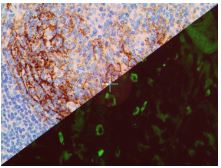

Bio SB has developed a highly sensitive Immunofluorescence and non-biotin monovalent Fab micropolymer IHC detection systems for the detection of IVD antibodies for Complement (C1q, C3c, C3d, C4c, C4d), Serum Proteins (Albumin and Fibrinogen) and Immunoglobulins (IgA, IgD, IgE, IgG, IgM, Kappa and Lambda) related to autoimmune conditions. Our innovative IF and IHC detection systems and high affinity antibodies, have opened the doors for a faster and accurate Immunofluorescence and Immunohistochemistry applicable to Autoimmune Disease like Nephropathies and Lupus.

These antibodies and detection systems are intended for use in Immunohistochemical (IHC) and Immunofluorescence (IF) applications of formalin-fixed paraffin-embedded tissues (FFPE), frozen tissue sections and cell preparations.

InDirect Immunofluorescence Detection

Rabbit FluoroDetector FITC |

Rabbit FluoroDetector FITC with FluoroMounter |

Rabbit FluoroDetector FITC with FluoroMounter with DAPI |